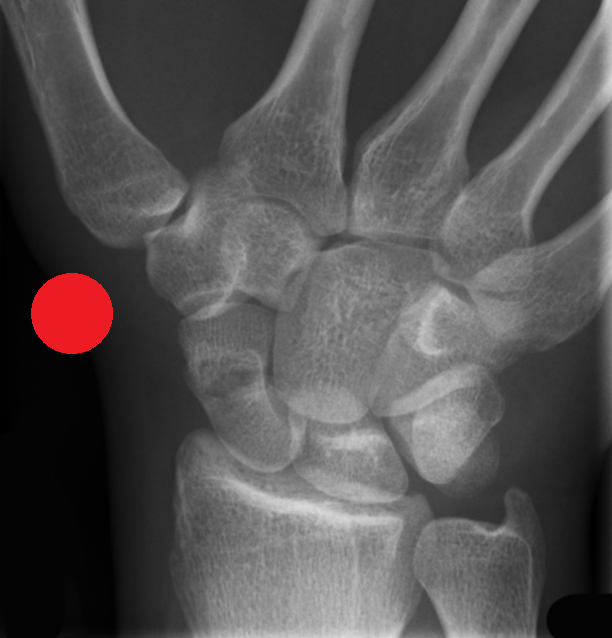

MSK CASES

www.mskradiology4u.co.uk

Red Dot X-Ray Interpretation Course (Two Days Online)

The course focuses on the identification and escalation of suspected pathology, fractures, or other deviations from normal imaging appearances. Participants will build robust knowledge and improve their ability to flag potentially critical findings.

The course focuses on improving the skills needed to identify a range of acute pathologies on x-rays, including fractures, dislocations, chest abnormalities and more. The course will improve patient safety by reducing missed urgent findings, especially whilst waiting for report completion.

• Improved identification of key radiographic features of common acute pathologies, eg. fractures, dislocations, pnemothorax.

• Improved ability to distinguish between normal anatomical variants and common pathological findings on Radiographs.